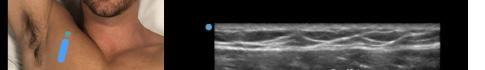

Image 1. Initial probe placement for the pectoralis nerve block I and II illustrated on a model: the blue line indicates transducer, and the green dot indicates directional marker corresponding to ultrasound image. Image 2. Final probe placement prior to the pectoralis nerve block I and II: blue line indicates transducer, and green dot indicates directional marker corresponding to ultrasound image.

Image 3. Pectoralis nerve block I injection between the pectoralis major and minor muscles: arrow on patient model indicates needle direction; the green dot indicates directional marker, and yellow dots indicate injectate within the fascial plane. Image 4. Pectoralis nerve block II injection between the pectoralis minor and serratus anterior muscles: the arrow on patient model indicates needle direction; the green dot indicates directional marker; and yellow dots indicate injectate within the fascial plane.